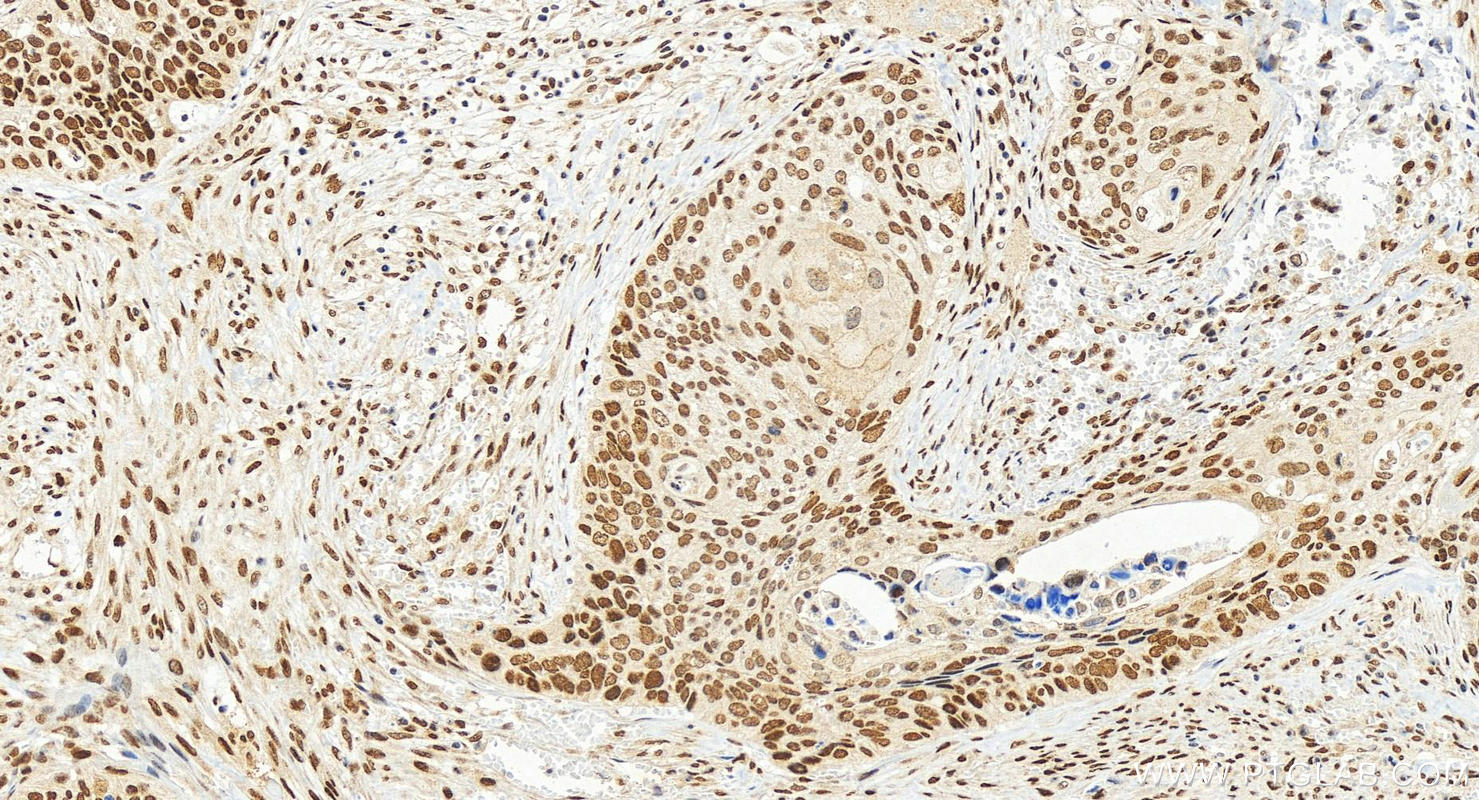

| Positive IHC detected in | mouse brain tissue, human cervical squamous cancer tissue Note: suggested antigen retrieval with TE buffer pH 9.0; (*) Alternatively, antigen retrieval may be performed with citrate buffer pH 6.0 |

| Immunohistochemistry (IHC) | IHC : 1:1000-1:4000 |